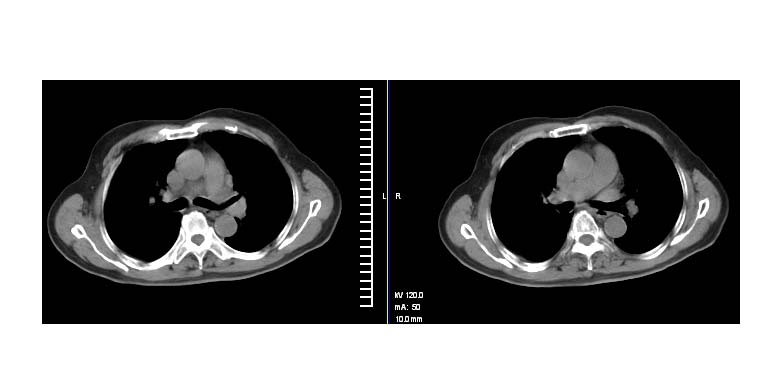

标题: CT11087:男性,82.咳嗽一周.抗炎治疗4-5天效果不明 [打印本页]

标题: CT11087:男性,82.咳嗽一周.抗炎治疗4-5天效果不明

左肺上叶尖段周围型肺癌伴左肺门淋巴结转移。

左上肺实质性肿块,浅分叶 毛糙 胸膜凹陷征 纵隔淋巴结肿大——支持:左肺上叶周围型肺癌!

左上肺软组织肿块,有分叶,短毛刺,气管旁间隙见有肿大淋巴结,考虑左上周围型肺癌伴纵隔淋巴结转移。

左肺上叶前段肺癌并纵隔淋巴结肿大。